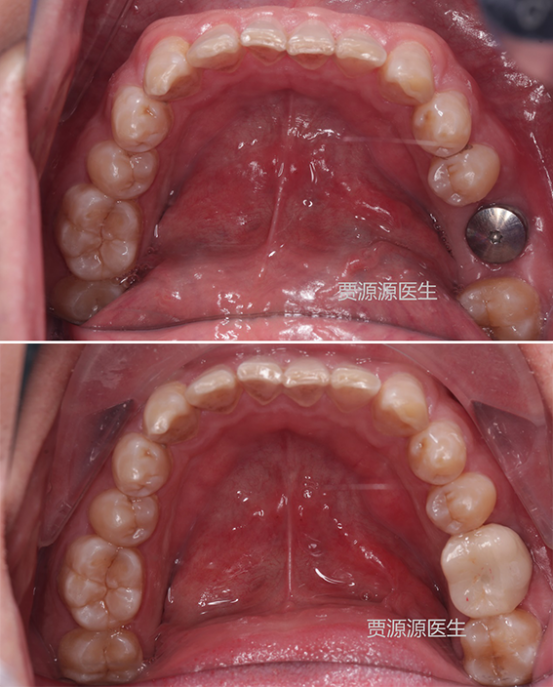

(嵌体修复)

(种植修复)